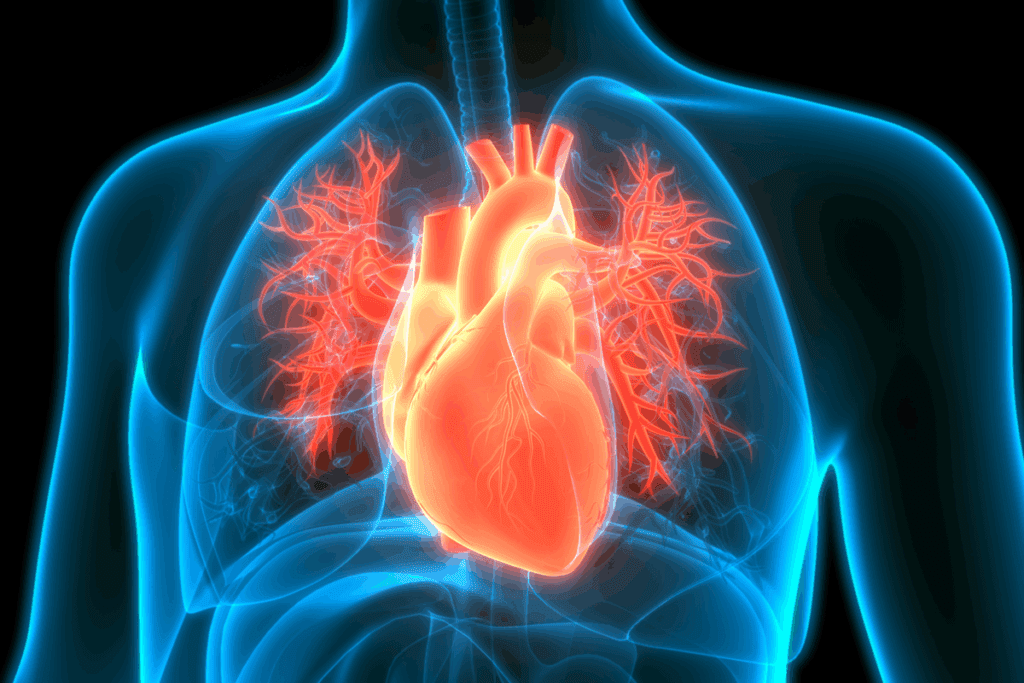

ECG third degree av block atrioventricular (AV) block, also known as complete heart block, is a serious heart condition. It stops electrical signals from the atria from reaching the ventricles. This makes the atria and ventricles beat on their own, a condition called AV dissociation.

Third-degree AV block, also known as complete heart block, is a serious heart condition. It needs immediate medical help. This condition causes AV dissociation, where the heart’s upper and lower chambers beat at different rates. This can lead to severe problems.

Definition and Pathophysiology

Third-degree AV block stops the electrical signals from moving between the heart’s upper and lower chambers. This means the chambers work on their own, leading to AV dissociation. The upper chambers beat normally, but the lower chambers beat slower, usually between 40-60 times per minute.

In third-degree AV block, the atria and ventricles beat on their own. The atria are controlled by the SA node, leading to a normal P wave rate of 60-100 bpm.

The ventricles, though, are controlled by an escape pacemaker. This can be in the AV junction or the ventricles themselves. The ventricular rate is slower, usually 40-60 bpm if the pacemaker is junctional.